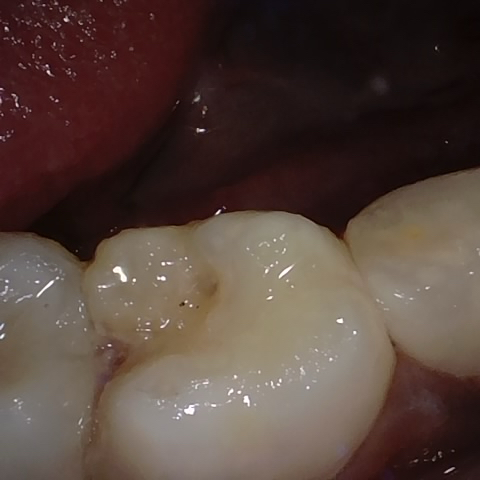

Annotated as "Good"